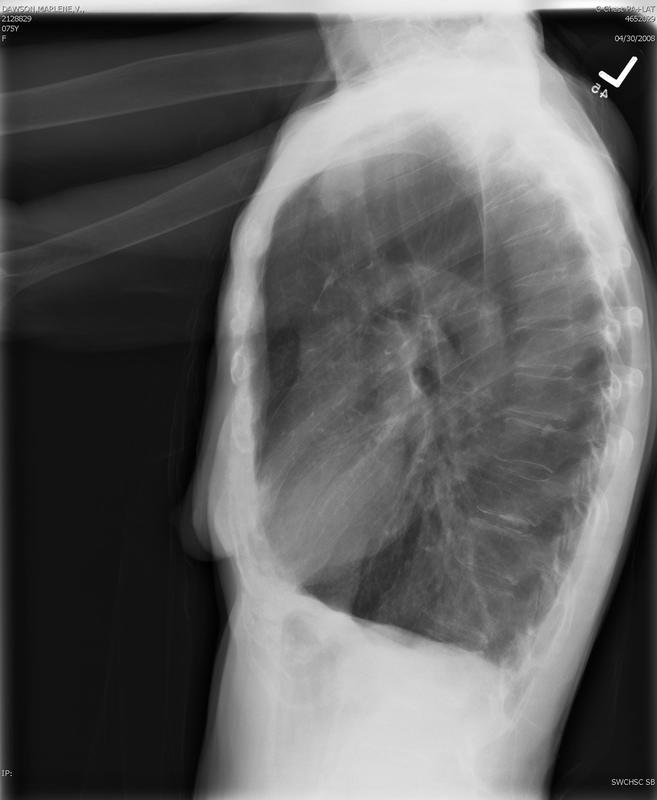

Emphysema Lat